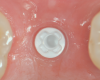

Fig 9. Healed implant site 12 weeks after surgery before re-entry.

Figure 9